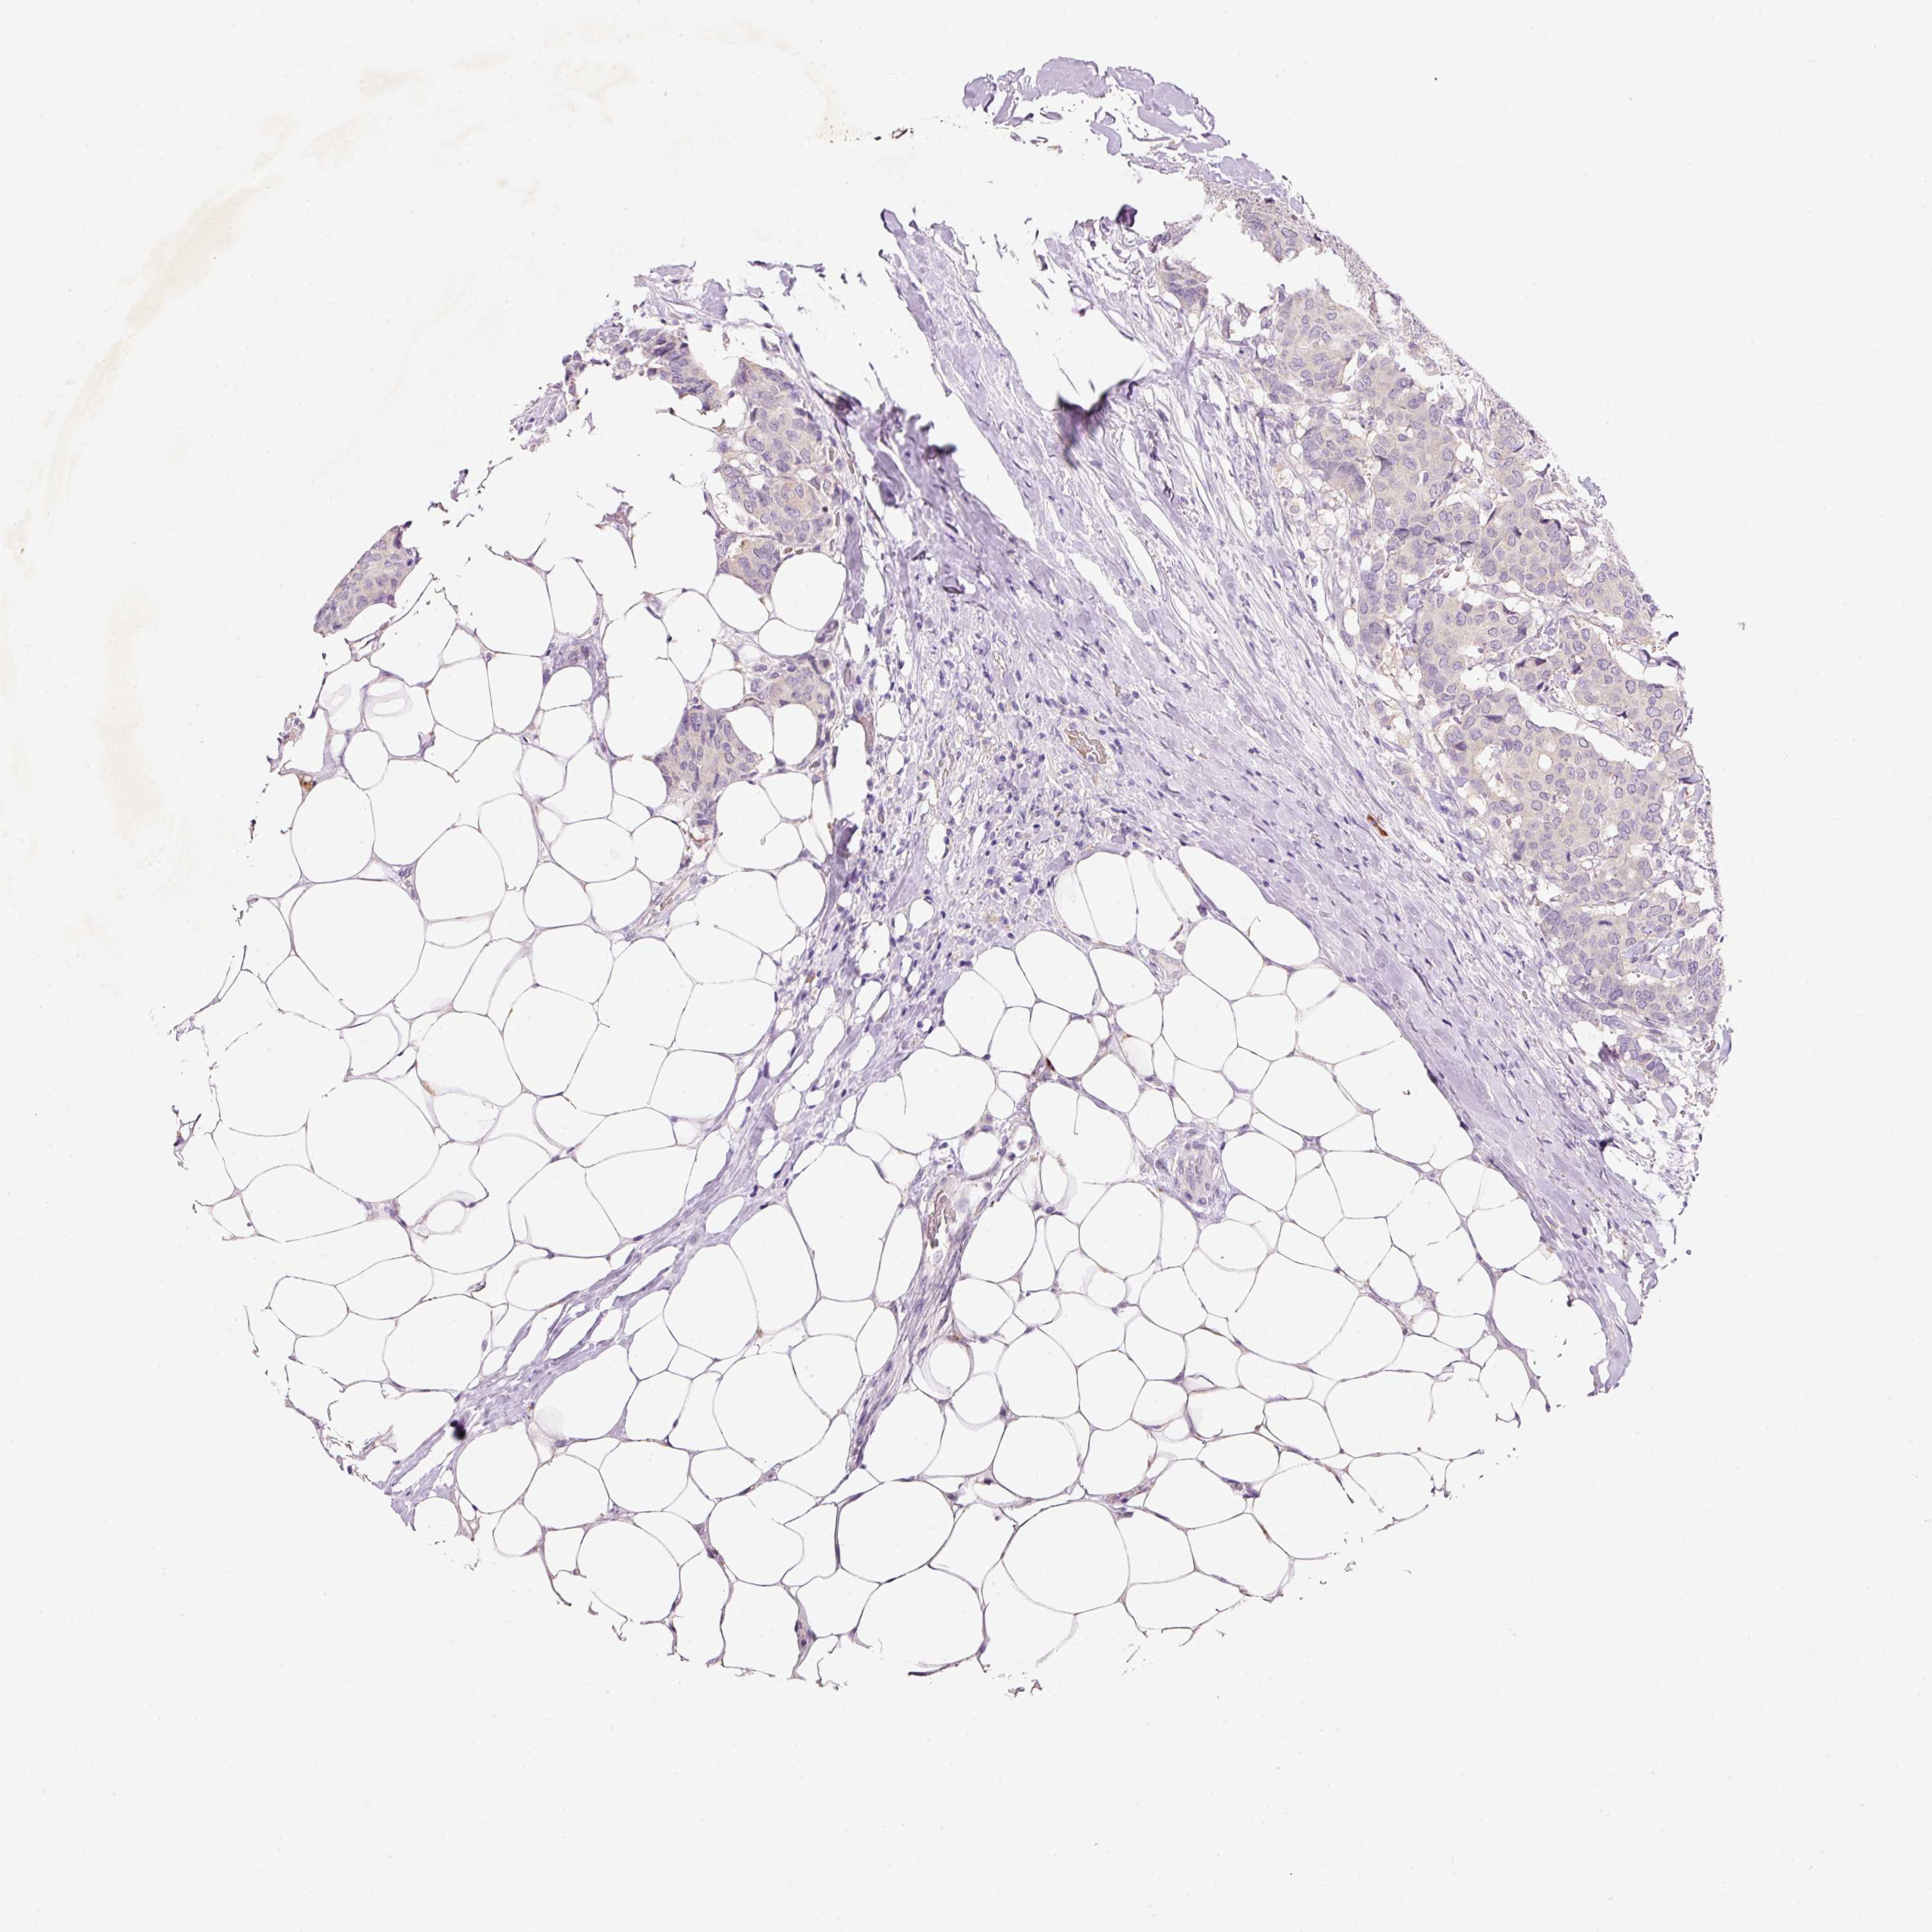

CANCER BREAST CANCER Show tissue menu

BRCA TCGA BRCA VALIDATION PROTEIN EXPRESSION

ANTIBODIES

AND

VALIDATION